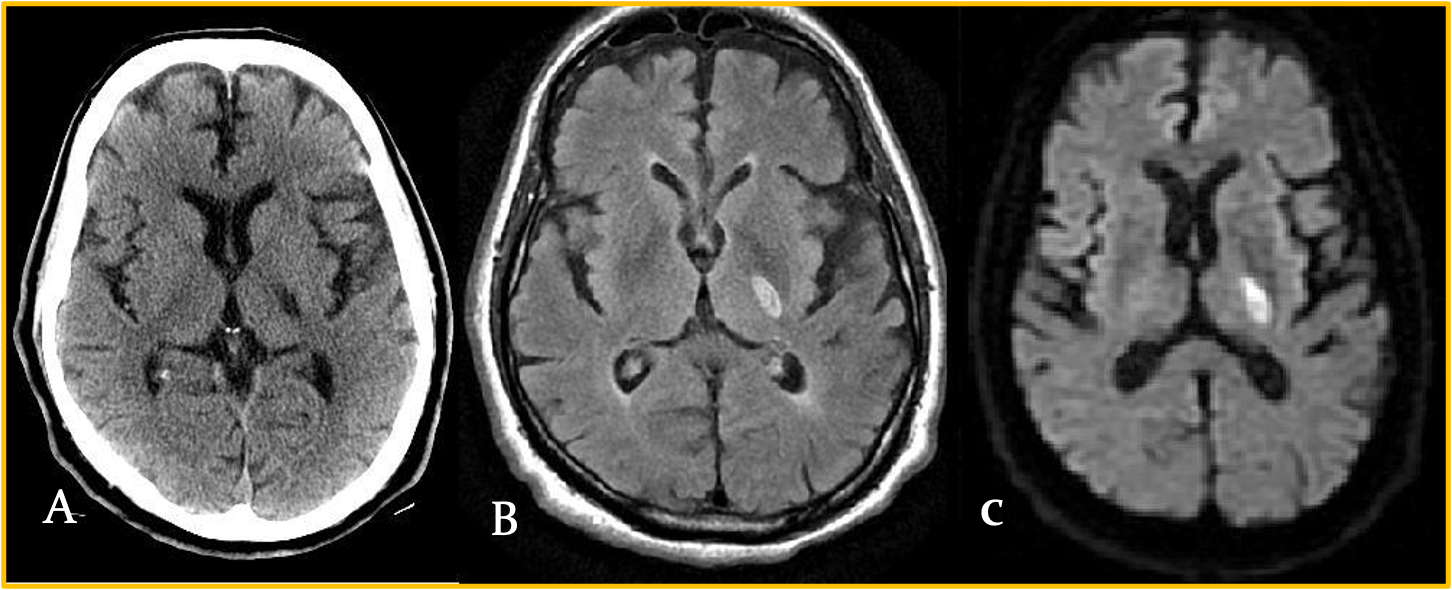

Acute lacunar infarct. A: Axial unenhanced CT image demonstrates an ovoid area of hypo density centered in the posterior limb of the left internal capsule. B: A corresponding DWI image demonstrates high-signal intensity, reflecting restricted diffusion in an acute lacunar infarct

LACUNAR INFARCTS

Axial NCCT scan: Demonstrates a focal area of hypodensity in the left posterior limb of the internal capsule in a 60-year-old man with acute onset of right-sided weakness.

High signal FLAIR sequence (middle image) and diffusion-weighted magnetic resonance imaging (MRI) scan (right image), with low signal on the apparent diffusion coefficient (ADC) maps indicating an acute lacunar infarction.

Lacunar infarcts are typically no more than 1.5 cm in size and can occur in the deep gray matter structures, corona radiata, brainstem, and cerebellum.